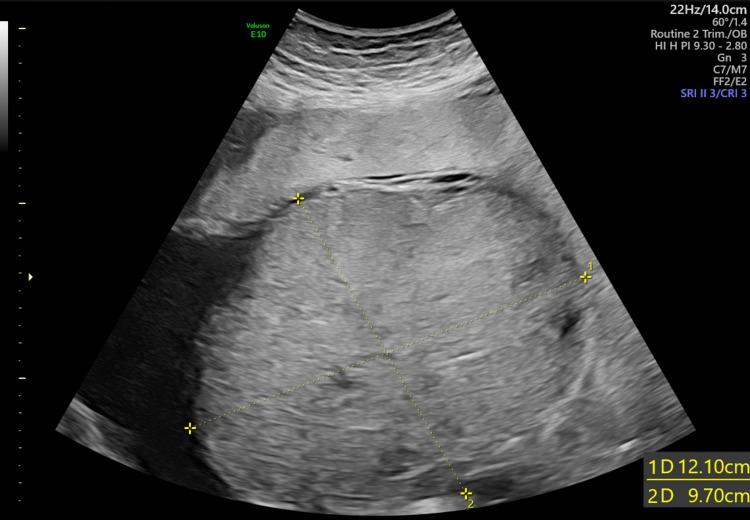

Chorioangioma is a benign placental neoplasm seen in about one percent of all pregnancies. The larger neoplasms generally cause severe foeto-maternal complications. We are reporting a case of a 33-year-old gravida three para two female who was incidentally diagnosed with chorioangioma at her routine 28-week antenatal follow-up. She delivered a preterm small-for-gestational-age female baby at 34 weeks with complications. Therefore, an early diagnosis warrants a close follow-up and timely intervention for a better outcome of the pregnancy.

绒毛膜血管瘤是一种良性胎盘肿瘤,在所有妊娠中约占1%。较大的肿瘤通常会导致严重的母婴并发症。我们报告一例33岁、孕3产2的女性病例,她在28周常规产前检查时被意外诊断为绒毛膜血管瘤。她在34周时早产了一名小于胎龄的女婴,并伴有并发症。因此,早期诊断需要密切随访并及时干预,以获得更好的妊娠结局。